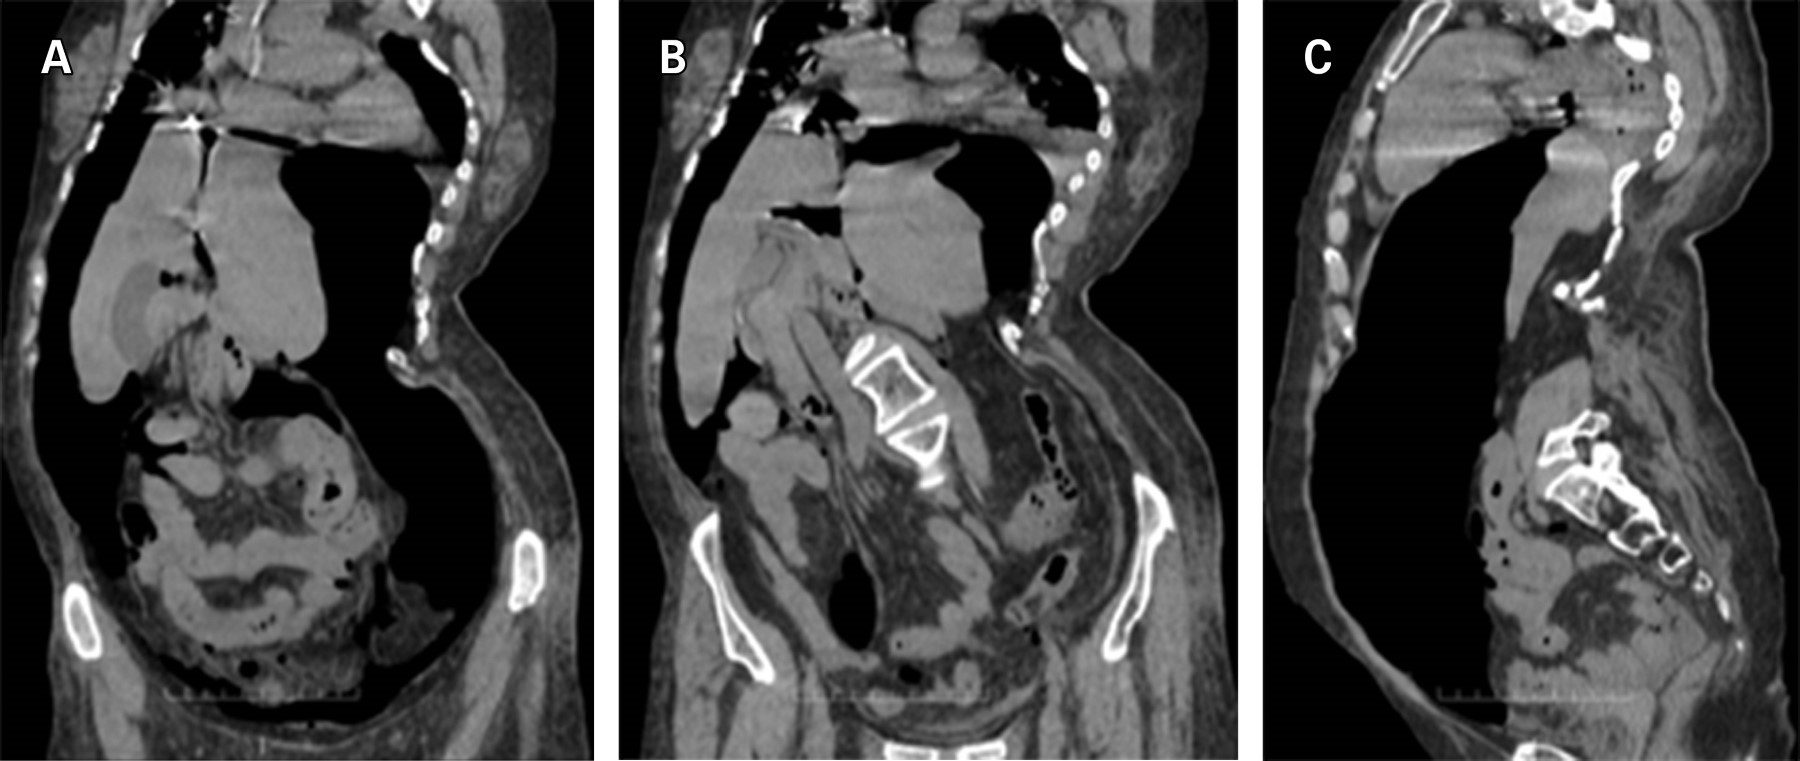

Posterior al estudio, presenta dolor abdominal intenso, distensión abdominal dolorosa y aumento del requerimiento de oxígeno de 3 a 5 L/min. El examen físico detecta taquicardia, abdomen poco depresible, timpánico, doloroso en forma universal, y ruidos intestinales presentes, disminuidos en frecuencia e intensidad. Como parte de su manejo, se solicita tomografía axial computarizada abdominal sin contraste; se evidencia neumoperitoneo y desplazamiento de órganos intraabdominales, así como malformación de cuerpos vertebrales dorsolumbares con rotación de estructuras abdominales (Figuras 2 y 3).

Figura 2

Figura 3